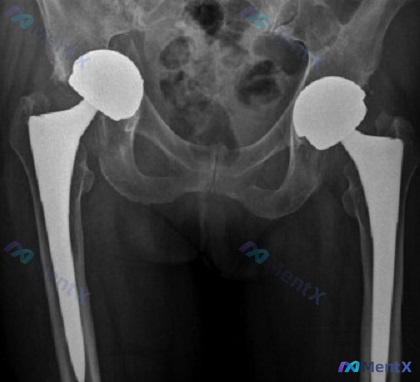

提供的是骨盆及髋关节正位X光片:

- 双侧均可见 THA 假体影,股骨柄居中,髋臼杯、股骨头对合可

- 报告写「无明显假体柄松动/断裂、无脱位、骨盆环连续、未见明显骨折线」

- 仅提示假体周围部分骨小梁略稀疏